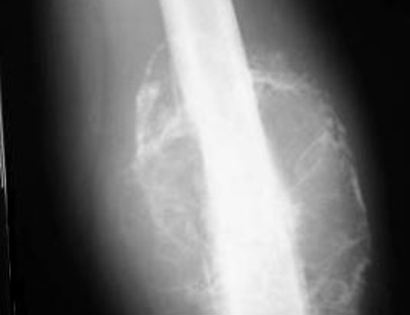

Distal Femur X-ray of Tumor

This is an x-ray image of the lower femur bone. The lighter area surrounding the bone is all tumor growth.